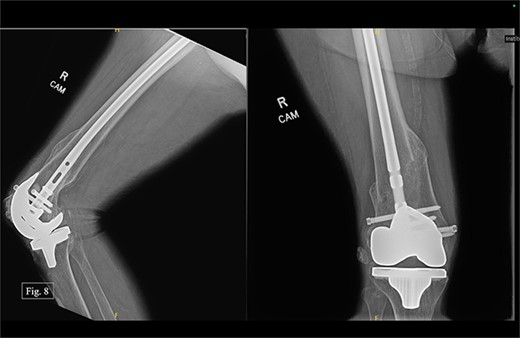

During her most recent visit in February 2024, 17 months post-op on the right, bilateral AP, right & left lateral, right & left AP, and full leg-length X-rays were taken. When looking at the right AP and lateral imaging, she had findings of progressive bone healing, maintained surgical alignment, and all hardware was intact (Fig. 8). Further, when looking at the bilateral AP and full leg length imaging, she had maintained hip alignment, equal leg length, and no changes in valgus or varus leg alignment (Figs 9 and 10). The patient reported a resting right knee pain of 1/10 and an ambulatory right knee pain of 2/10 with a full ROM. She was instructed to continue at-home physical therapy and NSAIDs as needed for pain and to return to the clinic in 6 months for further evaluation.